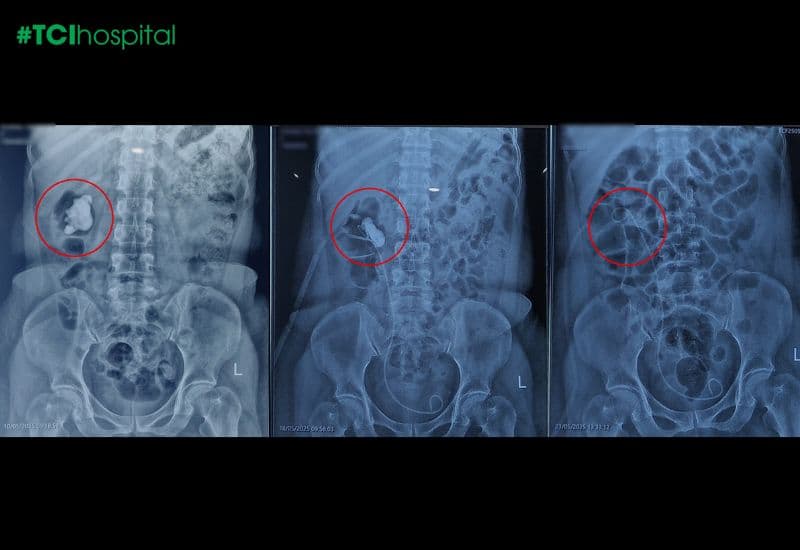

Bà H.T.H (61 tuổi, Đồng Hỷ, Thái Nguyên) đã xuất viện trong trạng thái khỏe mạnh, tinh thần nhẹ nhõm sau khi được lấy sạch viên sỏi thận cứng, găm chặt trong bể thận phải nhiều năm. Viên sỏi kích thước lên tới 34×36mm, khi được lấy ra ngoài cơ thể sau hai lần tán sỏi qua da đường hầm nhỏ bằng laser tại Bệnh viện ĐKQT Thu Cúc TCI, đã khiến chính các bác sĩ cũng phải bất ngờ vì hình dạng trên phim chụp như “cục đá vôi”, nhưng kết cấu “rỉ sét” đặc trưng của một khối tích tụ lâu năm.

Ngày 15/5, ca tán sỏi đầu tiên diễn ra thuận lợi, một nửa khối sỏi được lấy ra ngoài. Tuy nhiên do kích thước ban đầu lớn và sỏi rắn chắc nên cần xử lý khéo léo để gỡ sỏi triệt để nhưng vẫn bảo toàn nhu mô thận, ngày 18/5, bà H. tiếp tục được thực hiện phiên can thiệp lần hai để loại bỏ các mảnh sỏi còn sót lại.

Ba ngày sau đó, kết quả kiểm tra xác nhận sỏi đã được lấy sạch hoàn toàn. Bà H. được xuất viện trong trạng thái ổn định, không còn cảm giác đau tức, ăn ngủ tốt và tinh thần phấn chấn.